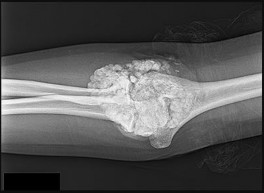

What is the diagnosis?

This patient has a dedifferentiated liposarcoma within a preexisting atypical lipomatous tumor. The imaging demonstrates a large fatty mass with increased internal septations proximally (the atypical lipomatous tumor) and a solid enhancing mass distally (the dedifferentiated portion). A biopsy reveals a high-grade liposarcoma. The other diagnostic responses do not reflect sarcomatous transformation of the lesion.